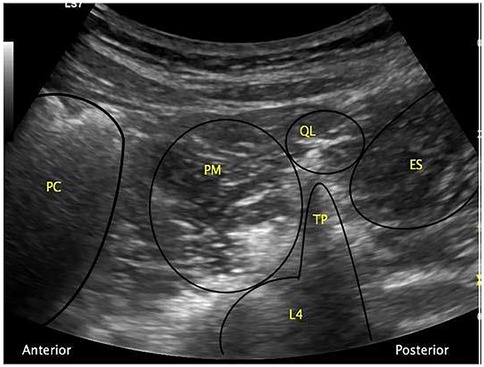

In clinical practice, a curvilinear ultrasound probe (2–6 MHz) is most frequently used; however, in thinner patients, a linear probe may be sufficient. When the probe is positioned transversely above the iliac crest, the characteristic “shamrock sign” becomes visible, serving as a key sonographic landmark (Figure 2) (3436).

Ultrasound image showing labels of muscle groups and structures. From left to right: PC (Psoas Major Muscle), PM (Psoas Major), QL (Quadratus Lumborum), TP (Transverse Process), ES (Erector Spinae). Anterior and posterior orientations are marked.

Figure 2. The “shamrock sign” obtained with a curvilinear ultrasound probe. ES, erector spinae muscle; L4, fourth lumbar vertebra; PC, peritoneal cavity; PM, psoas muscle; QL, quadratus lumborum muscle; TP, transverse process [Reproduced from Nee and McDonnell (35). © 2025 World Federation of Societies of Anaesthesiologists. Distributed under the Creative Commons Attribution License, CC BY 4.0].